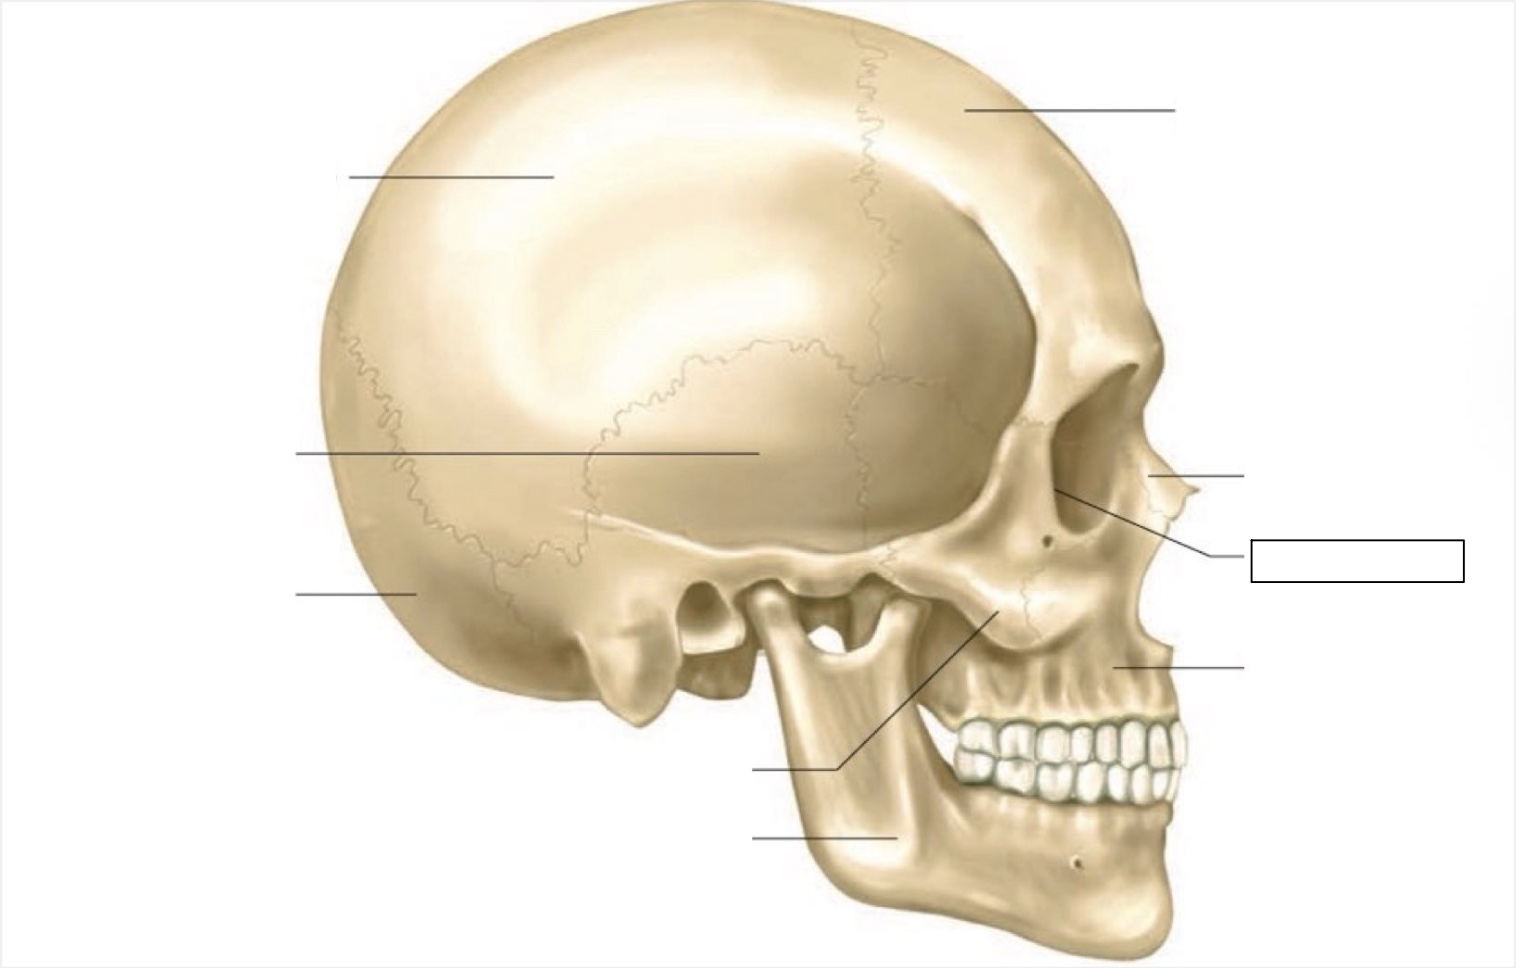

skull

frontal bone

nasal bone

orbit

maxilla

mandible

zygomatic bone

occipital bone

temporal bone

parietal bone